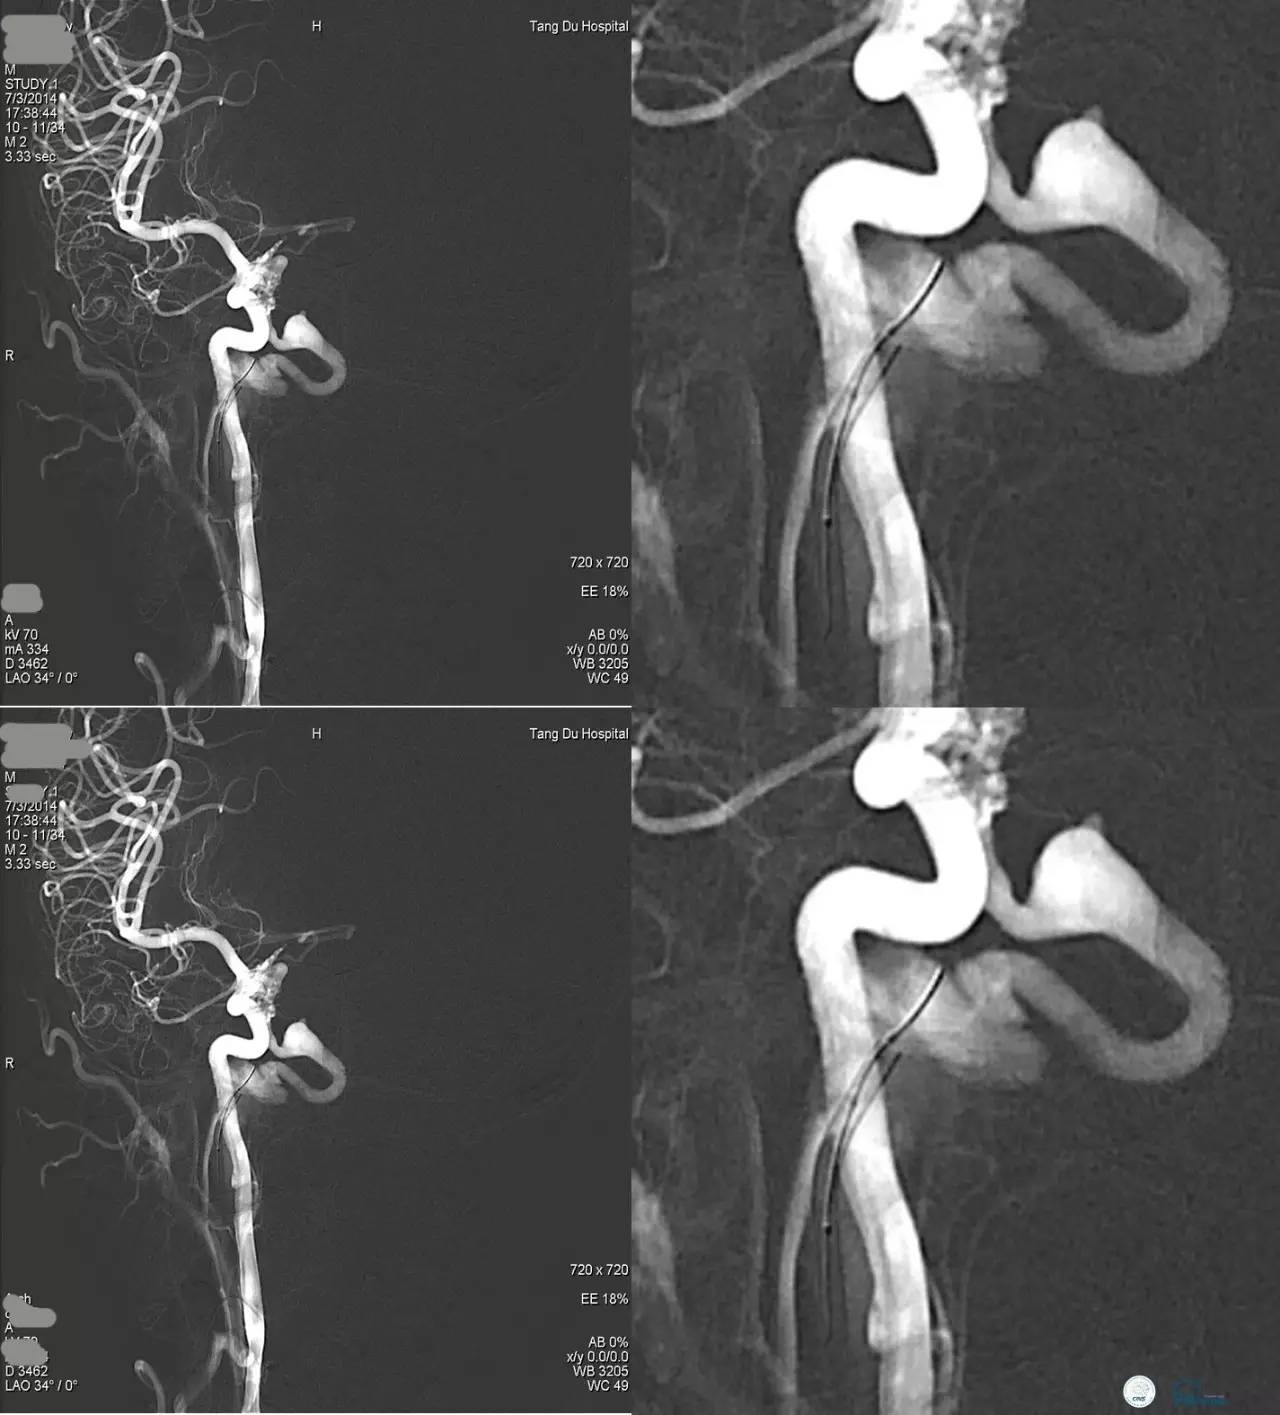

乙状窦区的DAVF,供血动脉细小,静脉引流道通畅。

同侧颈内静脉试图进入引流静脉,但是由于角度问题非常困难。

从对侧颈内静脉绕路进入引流静脉。

Sceptor球囊导管到达静脉内,充盈球囊,让后注入Onyx。

术后造影提示DAVF治愈。